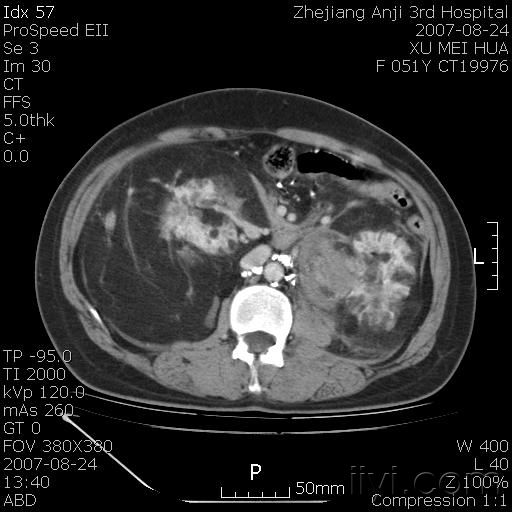

以下是引用还珠格格在2007-8-27 10:19:00的发言:[br]双侧肾脏形态失常,可见巨大的以低密度脂肪为主的混合性肿块,占据中下腹,残留的肾组织轻度强化,增强后肿块内实质部分呈峰窝状强化,低密度区无强化。另左侧肾盂轻度积水。根据病史 考虑 双肾血管平滑肌脂肪瘤可能性大。[br] 鉴别诊断 1、脂肪瘤,境界清楚,肿块内完全是脂肪,几乎没有软组织成分; 2、畸胎瘤:罕见,除有软组织成分外,另一特征是有钙化或骨化影组织。